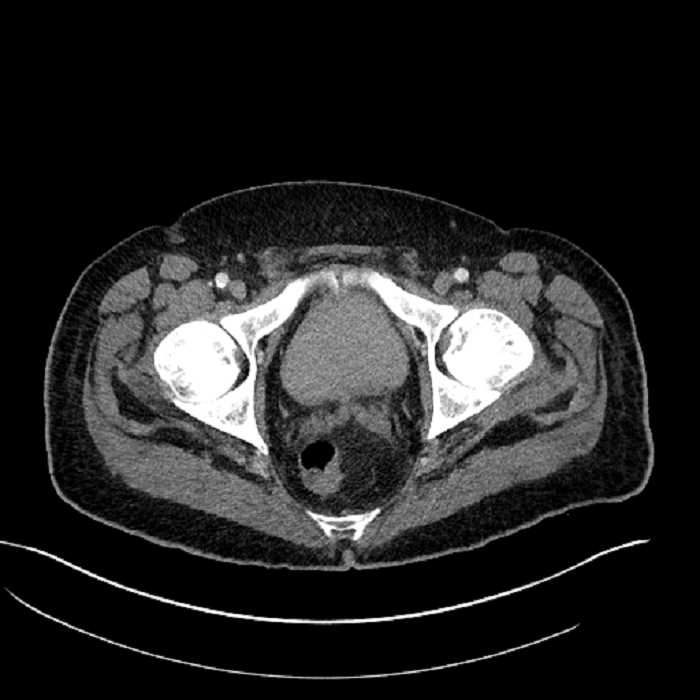

• Mild mural thickening of a segment of the sigmoid colon with adjacent fat stranding and a 1.5 cm fluid and gas collection along the tip of an inflamed diverticulum

• Loss of the normal fat plane between this collection and adjacent loops of small bowel, which demonstrate mural thickening

• High grade stenosis of the left common iliac artery, with the left internal and external iliac arteries remaining patent

Acute sigmoid diverticulitis complicated by a small contained perforation and a large abscess in the right hepatic lobe. Additional small subcapsular abscesses along the anterior margin of the left hepatic lobe.

Additionally, loss of the normal fat plane between the peridiverticular collection and adjacent thickened loops of small bowel raises the potential for an enterocolonic fistula.

High grade stenosis of the left common iliac artery. The left external and internal iliac arteries are patent.

Hepatic abscess showing the double target sign with low density internally surrounded by a thin inner enhancing rim (red arrow) and ill-defined outer low density rim (yellow arrow). Blue arrow indicates an internal septation. Red arrows: additional smaller subcapsular abscesses. Red arrow: focal contained perforation associated with diverticulitis.